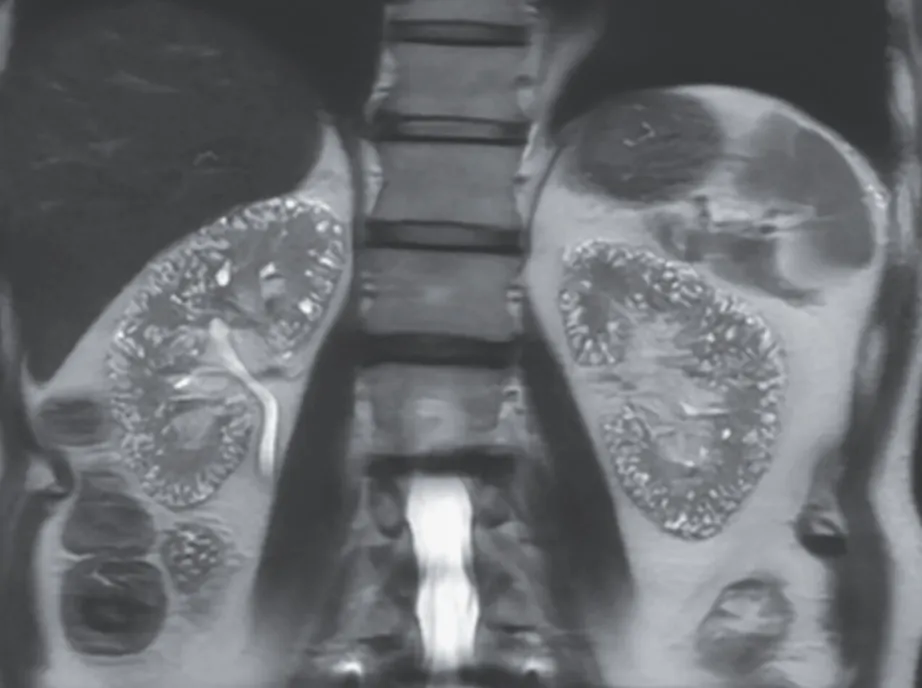

As radiografias simples do ombro direito e da mão esquerda mostraram massas calcificadas multilobuladas e bem

definidas (Figura 2, A e B), compatíveis com calcinose tumoral. A realização e cintilografia de glândulas

paratireoides identificou hiperplasia das 04 glândulas.

Radiografia simples . (A) Radiografia do ombro direito mostrou calcificação amorfa, multilobulada e cística em localização periarticular. (B) A radiografia da mão esquerda mostrou calcificação amorfa e multilobulada ao redor das articulações interfalângicas promixais do primeiro dedo.